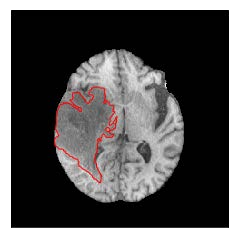

Machine learning has been widely adopted for medical image analysis in recent years given its promising performance in image segmentation and classification tasks. The success of machine learning, in particular supervised learning, depends on the availability of manually annotated datasets. For medical imaging applications, such annotated datasets are not easy to acquire, it takes a substantial amount of time and resource to curate an annotated medical image set. In this paper, we propose an efficient annotation framework for brain MR images that can suggest informative sample images for human experts to annotate. We evaluate the framework on two different brain image analysis tasks, namely brain tumour segmentation and whole brain segmentation. Experiments show that for brain tumour segmentation task on the BraTS 2019 dataset, training a segmentation model with only 7% suggestively annotated image samples can achieve a performance comparable to that of training on the full dataset. For whole brain segmentation on the MALC dataset, training with 42% suggestively annotated image samples can achieve a comparable performance to training on the full dataset. The proposed framework demonstrates a promising way to save manual annotation cost and improve data efficiency in medical imaging applications.

翻译:近年来,由于在图像分割和分类任务方面表现良好,医学图像分析广泛采用了机器学习。机器学习的成功,特别是监督学习的成功,取决于手动附加说明数据集的可用性。对于医疗成像应用来说,这种附加说明数据集不容易获得,需要大量的时间和资源来翻译附加说明的医学成像集。在本文件中,我们建议为大脑MR图像建立一个高效的注释框架,为人类专家提供信息性样图像,供人类专家作说明。我们评估了两种不同的大脑图像分析任务的框架,即脑肿瘤分割和整个大脑分割。实验显示,对于BRATS 2019数据集的脑肿瘤分割任务,培训一个只有7%的附加说明图像样本的分解模型,其性能与全数据集培训的性能相当。对于MALC数据集的整个大脑分割,用42%的附加说明性图像样本进行的培训,可以实现与全数据集培训的类似性能。拟议的框架展示了节省人工注解成本和提高医疗成像应用数据效率的有希望的方法。